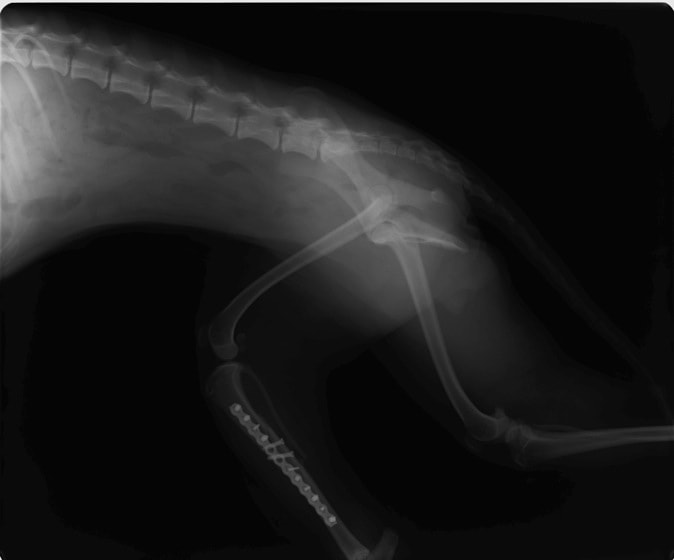

症例:交通事故による椎体脱臼

柴犬:9歳、避妊雌

交通事故直後、胸腰部に激しい疼痛、両後肢に完全麻痺を認め、シェフシェリントン徴候を呈していました。レントゲン検査において、第11-12胸椎間の脱臼が認められました。

脊髄の減圧、脊柱管の再構築・安定化を目的に、片側椎弓切除術およびMatrixMANDIBLE Plateによる椎体固定を実施しました。

隣接椎体を架橋するようにプレートを設置しました。

術後レントゲン写真